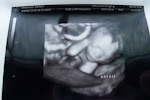

We saw a well known high risk dr today so we would have a plan b incase I went into labor early because at the hospital my dr delivers they at don't take babies under 30 weeks. The dr today took a look at everything and saw the kidneys and although the fluid looked like it had increased in each kidney he was not concerned. He also said that the amniotic fluid looked normal to him. On his machine it showed Roman measured 2 lbs 10 ounces which is what he weighed last week. He said he wasn't concerned and that that happens when you do measurements every week. Were going to see him again on Tuesday and I asked if he would measure him again then and he agreed to do so. It showed Roman being in the 36th percentile. We'll see what Tuesday reveals. This is the 3rd night in a row where I have had consistent contractions. They start in my lower belly or my back and work their way around. Last night I was having 4 or 5 an hour and they lasted for about for about 6 or 7 hours. When I woke up this morning my back hurt so bad! He told me that I can double my procardia and if I have 6 or more an hour that I can go get an NST at the hospital. He checked to see if I'm dilated and I'm dilated about a fingertip. I am going to continue seeing both dr's and when the time comes...I can pick which one and which hospital I want to deliver at. This way I see them both each week and I'll get 2 opinions! Either way I really like both dr's and know I'm in good hands....Gods hands that is!